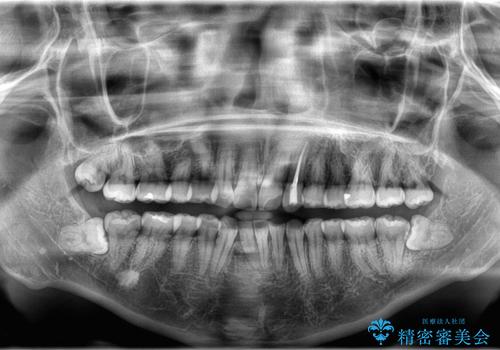

- 「歯の捻じれとがたつき」を主訴に来院された患者様です。

軽度な捻転と叢生だったため、インビザラインのモデレートで治療を行いわずか半年で治療を終える事が出来ました!

- 税込583,000円費用は治療当時の料金となります